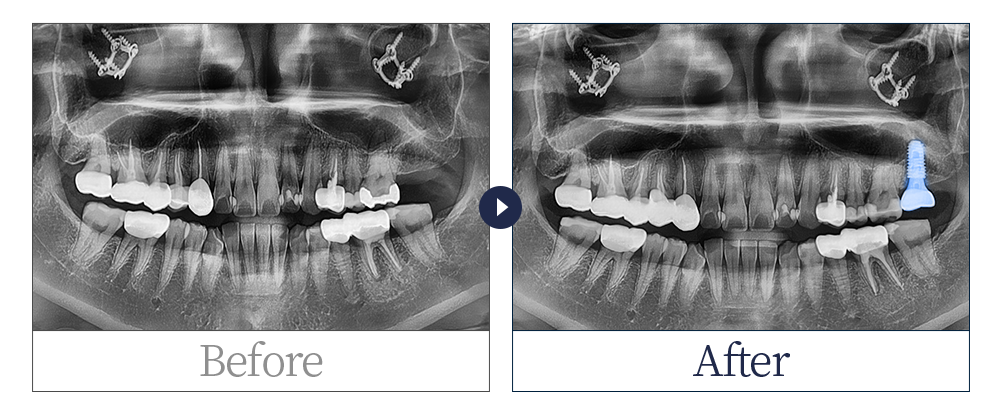

제목 30대 여 임플란트 식립 카테고리 임플란트

30대 여 임플란트 식립입니다.

치료 기간 : 1년 이상